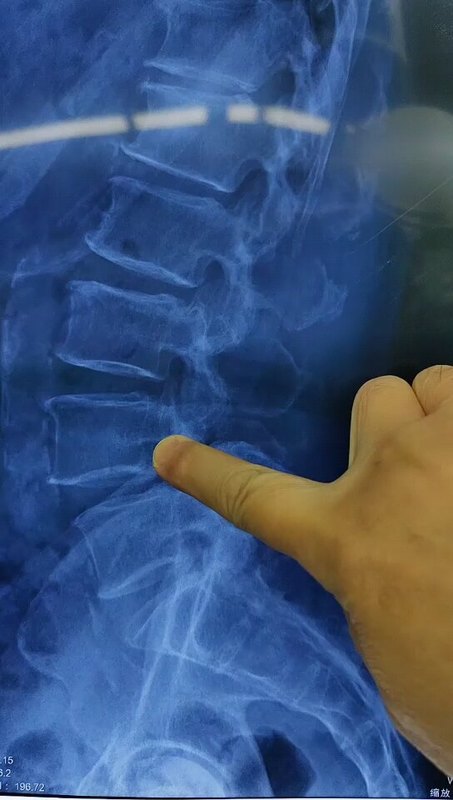

【医学科普】吓人的脊柱“拼接”片

江晓兵主任医师 广医二院 骨外科 脊柱外科

362人已读